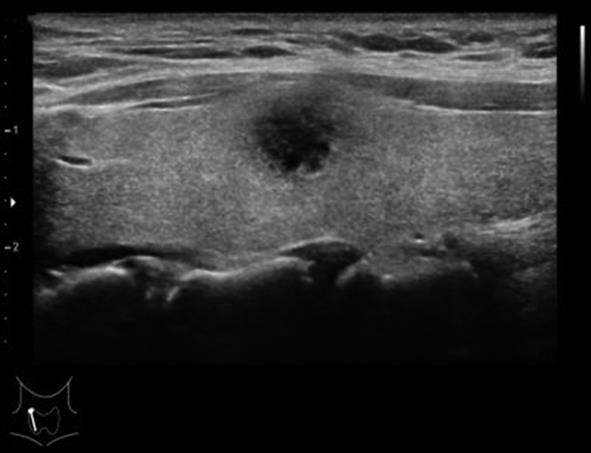

• 基于SEER数据库构建高危PTMC的诊断模型与验证

2023, 48(12):1418-1424. DOI: 10.13406/j.cnki.cyxb.003392

摘要 (71) HTML (47) PDF 1.64 M (177) 评论 (0) 收藏

摘要:目的 探讨高危甲状腺微小乳头状癌(papillary thyroid microcarcinoma,PTMC)的风险预测因子,构建可靠的列线图诊断模型并验证。方法 回顾性分析2004至2015年SEER数据库中手术治疗的PTMC患者(训练集)以及2020至2022年四川省人民医院甲状腺诊疗中心诊治的甲状腺微小结节患者(外部验证集)的临床病理及超声影像资料。验证集中,利用logistic回归分析高危PTMC的风险预测因子,构建列线图诊断模型并采用内部验证集和外部验证集分别进行验证。再根据术前超声影像学特征进行间接评估,探讨术前超声影像学特征预测高危PTMC的可行性与可靠性。结果 训练集纳入患者1 552例,外部验证集纳入患者516例。训练集中筛选出高危PTMC的独立危险因素为性别(男性)、年龄(≤55岁)、结节数目(多灶)、包膜侵犯,颈部淋巴结异常(P<0.05),构建出的列线图C指数为0.946。在训练集及外部验证集中,该列线图模型的预测结果与实际情况均具有较好的一致性。基于超声影像特征诊断高危PTMC的受试者工作特征(receiver operating characteristic,ROC)的曲线下面积(area under the curve,AUC)值为0.931(95%CI=0.910~0.953),与基于病理特征诊断的AUC值具有较高的一致性(κ=0.611,P<0.05)。结论 本研究构建的高危PTMC诊断模型具有较好的预测效应,利用术前超声影像学特征预测高危PTMC具有一定的临床可行性及临床应用价值。